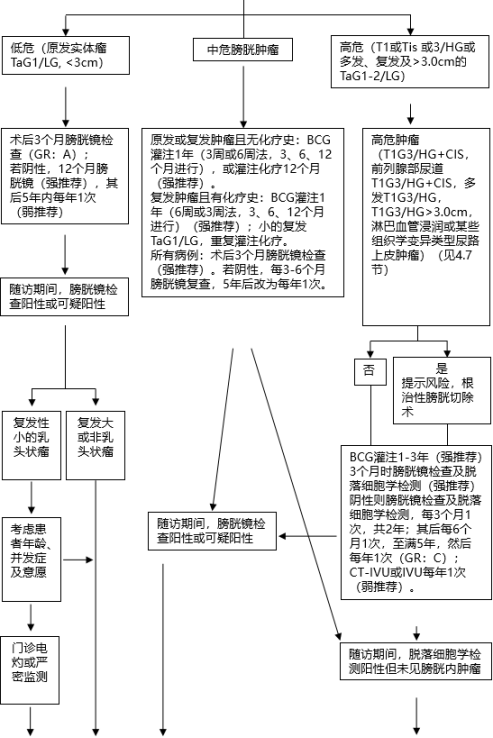

对于40岁以上出现无痛性肉眼血尿,结合患者既往有无膀胱疾病史、家族史、吸烟与环境接触史以及相关症状和查体结果做出初步判断,并进一步进行相关检查。

目前肌层浸润性膀胱癌的标准治疗方案为膀胱癌根治术+淋巴结清扫术,保留膀胱方案主要为经尿道膀胱癌电切术+术后卡介苗(bacilli calmette guerin,BCG)膀胱灌注。

BCG治疗期间或治疗后复发低级别肿瘤,不属于BCG治疗失败。

BCG膀胱灌注治疗失败病例分类: